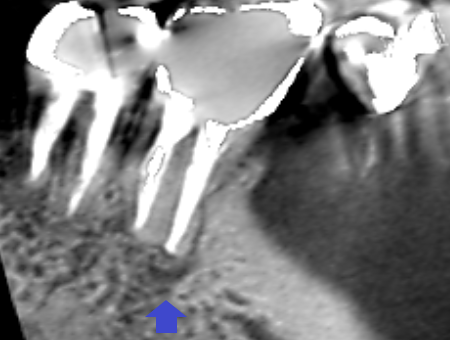

下顎第一大臼歯の矢状断のCT画像です。

矢印の下顎第一大臼歯の近心根の先に膿の影がみられます。